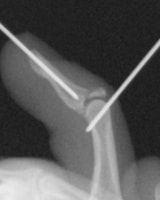

高精細デジタルX線イメージ

整形外科領域の手術において、骨を扱う際に必要なのがX線イメージです。当院では米ホロジック社製のフルオロスキャンを用いることにより、一般整形外科で用いる巨大なCアームでは見ることが困難な指骨の関節内骨折においても良好な整復操作を行うことを可能としています。